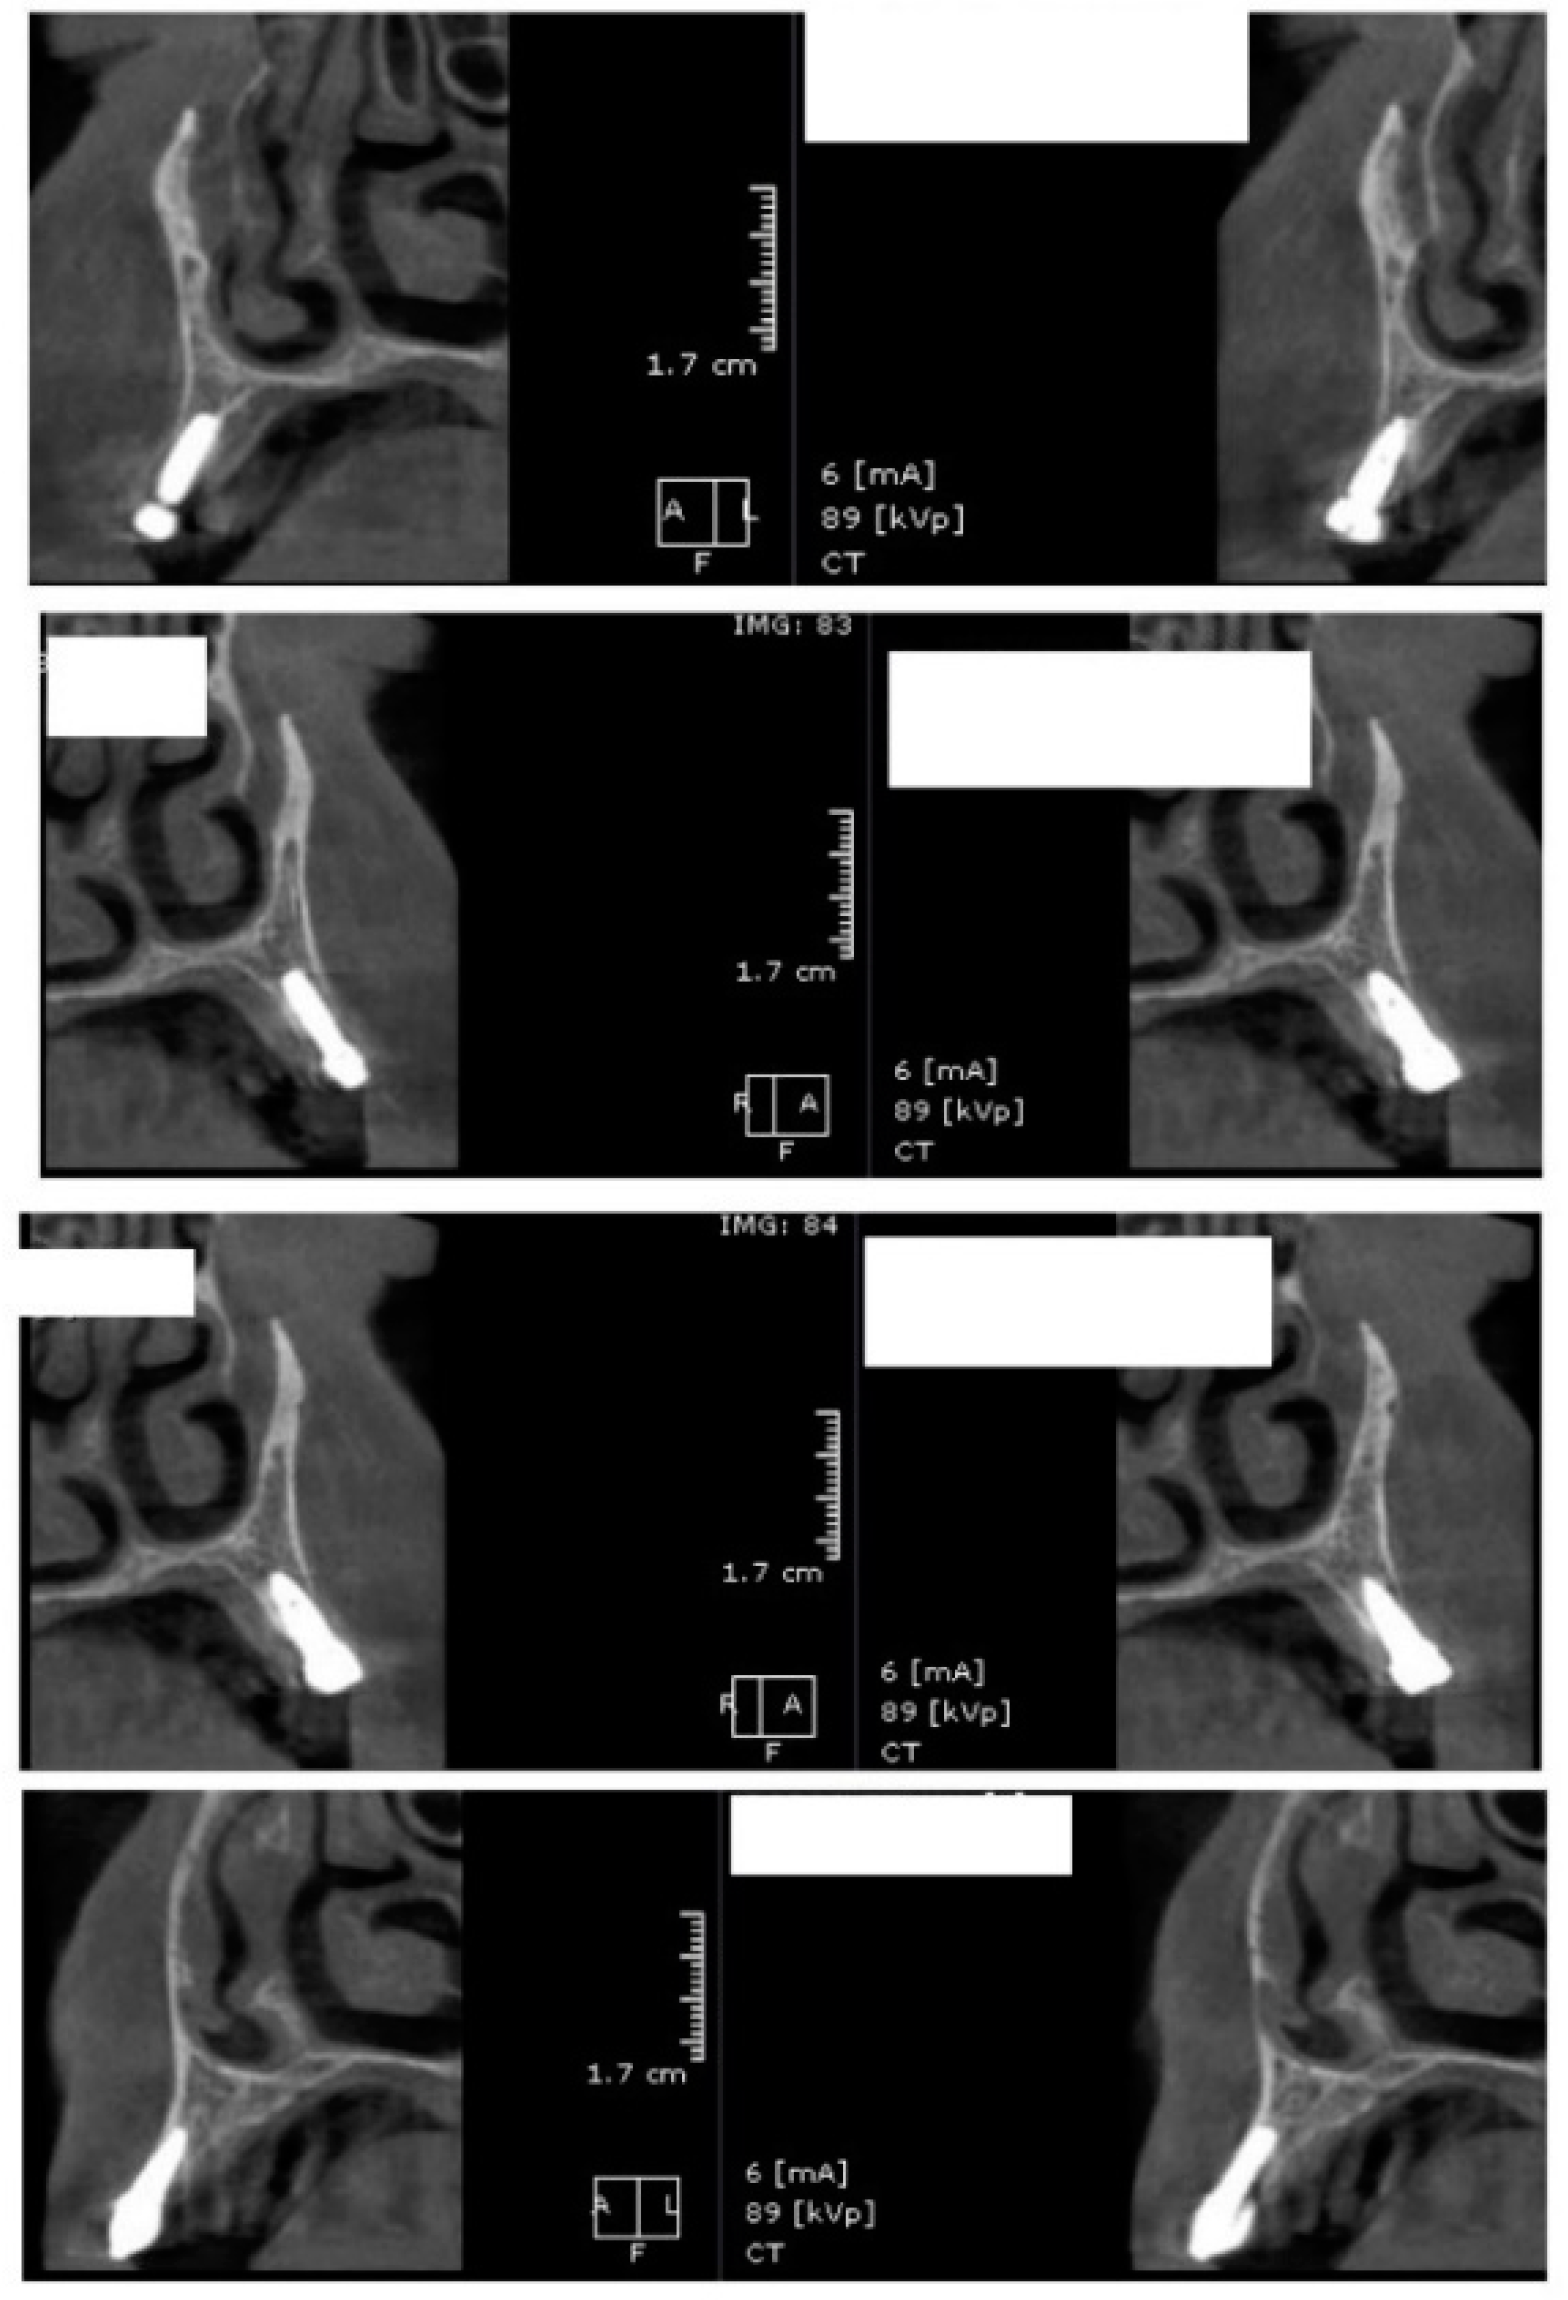

In the next phase of the study, after a healing period of 60 days, new measurements regarding bone density were recorded (Figure 12 and Figure 13). To avoid the metal artifact/beam hardening effect created by implants, new measurements were recorded at a 2 m distance from the implant site.

Figure 12.

Bone density around dental implants at 60 days following surgery with conventional healing caps.

Figure 13.

Bone density around dental implants at 60 following surgery with MED™ electromagnetic healing caps.